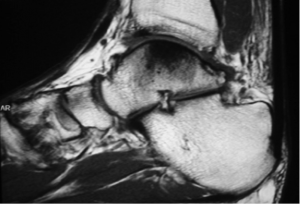

Masculino, 50 anos, Dor no Tornozelo

Histopatologicamente, descreve-se a presença de lesão na cartilagem articular desde a adolescência, podendo atingir 90% dos indivíduos aos 45 anos. Radiograficamente, considerando-se todas as articulações, a osteoartrite acomete cerca de 60% dos homens e 70% das mulheres após os 65 anos, sendo que, após os 85 anos essa cifra atinge 100% (vide imagem 1).

Frente a um paciente com o diagnóstico de osteoartrose, o médico deve estabelecer um programa terapêutico individualizado e multidisciplinar, objetivando reduzir os sintomas, melhorar a função e limitar incapacidades. Figura 1.